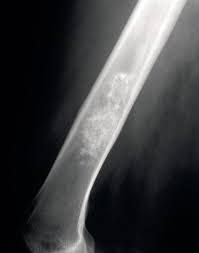

An enchondroma is a type of noncancerous bone tumor that begins in cartilage. Cartilage is the connective tissue from which most bones develop. Cartilage plays an important role in the growth process. There are many different types of cartilage in the body. An enchondroma most often affects the cartilage that lines the inside of the bones. It often affects the long, tiny bones of the hands and feet. It may also affect other bones such as the thighbone (femur), upper arm bone (humerus), or one of the two lower leg bones (tibia). An enchondroma may happen as one or several tumors. The health conditions that cause multiple tumors include: Ollier disease. This is when multiple areas in the body grow the tumors. Maffucci syndrome. This is a combination of multiple tumors and benign tumors made up of blood vessels (angiomas). Enchondromas are the most common type of hand tumor. They may affect a person at any age but are most common in people ages 10 to 20. They affect men and women equally.